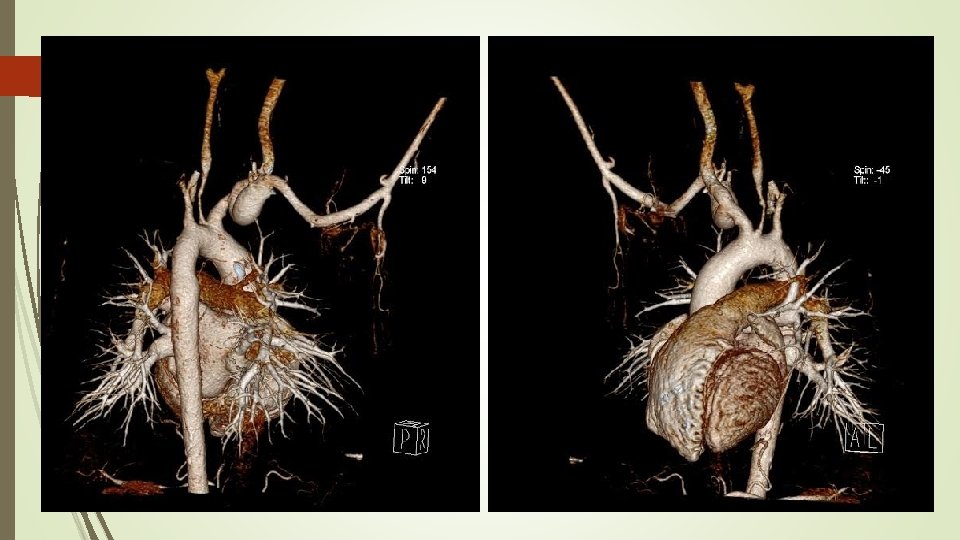

Angio. TAC aorta helicoidal sincronizado - Engrosamiento en forma de semiluna de aorta torácica ascendente y un engrosamiento circunferencial difuso de arco aórtico y aorta torácica descendente, alcanzando la bifurcación ilíaca. - Engrosamiento circunferencial del origen los troncos supraaórticos con estenosis filiforme del origen y primeros centímetros de carótida común izquierda. - Oclusión de arteria subclavia izquierda desde origen de arteria vertebral con repermeabilización de arteria axilar por colaterales. - Estenosis de la aorta abdominal en todo su recorrido siendo filiforme a nivel infrarrenal con diámetro mínimo de 5 mm. - Dilatación post estenótica ilíaca de común derecha. Hallazgos compatibles con Enfermedad Takayasu en fase crónica